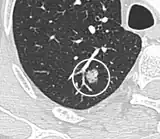

Lobulated nodule.[9] -

Spiculated lung nodule.[9] -

A "notch sign".[9] -

A triangular perifissural node can be diagnosed as a benign lymph node.[9]